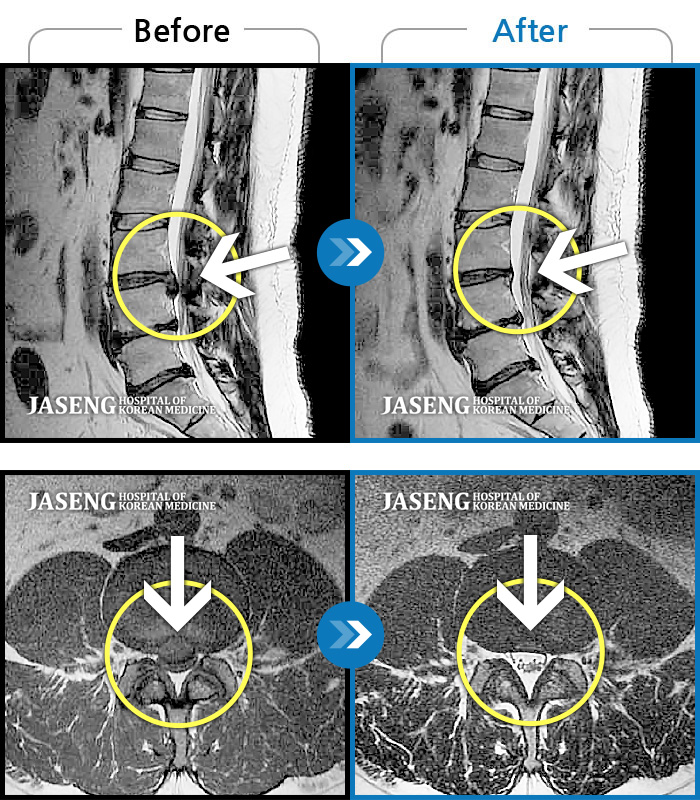

허리디스크

수원 · 김태성 원장

우측 허리 통증과 우측 다리 방사통으로 활동하기 힘든 상태

촬영시기

2021.02.03 ~ 2021.07.09

2022.03.25